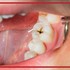

علائم کرم خوردگی دندان چیست و چگونه از آن جلوگیری کنیم؟

کرم خوردگی دندان تخریب ساختار دندان است و می‌تواند هم مینای دندان (پوشش خارجی دندان) و هم لایه عاج دندان را تحت تاثیر قرار دهد. ...